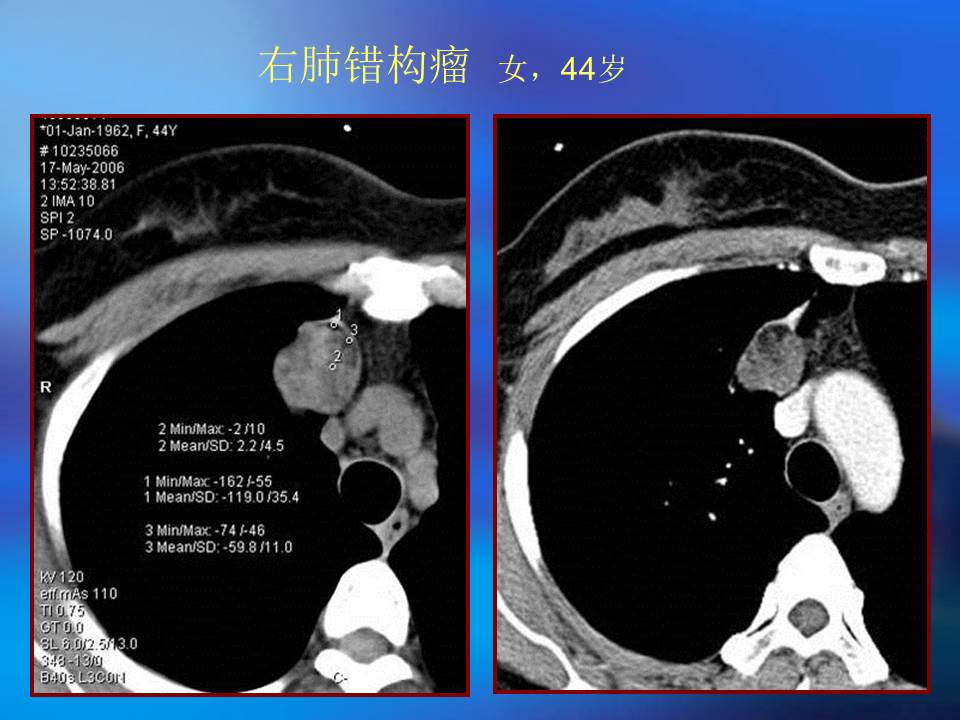

肺良性肿瘤